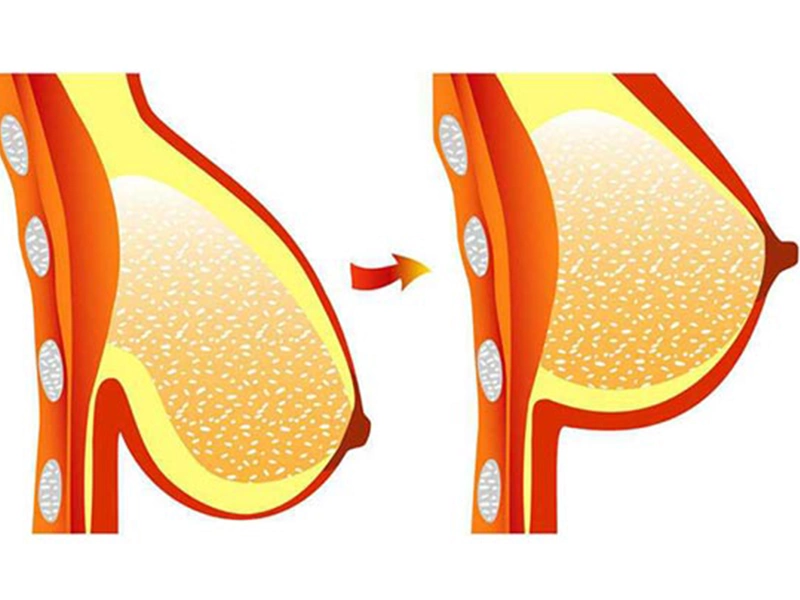

افتادگی سینه یکی از دغدغههای شایع در بین زنان پس از بارداری، شیردهی یا کاهش وزن شدید است. این وضعیت